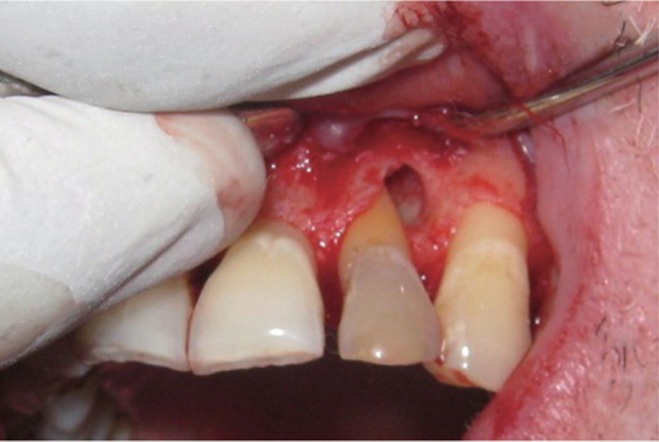

The area selected for surgery was anesthetized using xylocaine with adrenaline 1 : 200,000. A full thickness flap was raised at the labial aspect using intracrevicular incision (

Figure 5). Thorough curettage of the defect area was done and a combination of PRF and bioactive glass was placed in the defect (

Figures 6 and

Figure 5Curettage of the defect after reflection of soft tissue flap using intracrevicular incision.

Figure 6Placement of graft into defect.

Figure 7